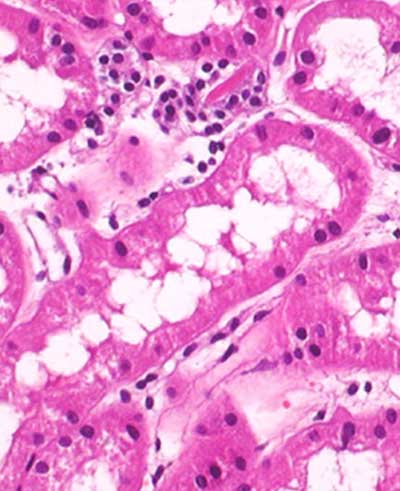

Histopathology

- Routine Staining (H & E)